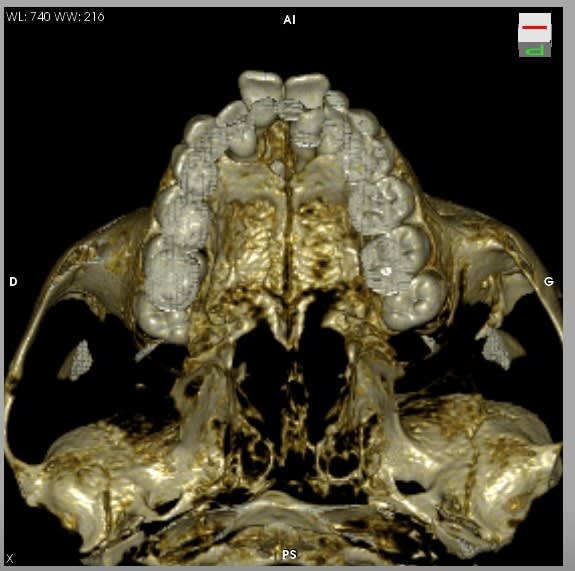

Allez, je lance le sujet, envoyez vos photos ou vidéo.

J'ai pu garder le paquet vasculo nerveux palatin antérieur. Les grincheux diront que çà sert à rien, mais j'avais le temps et je trouve çà classe :))

(le trou en palatin de la 21 c'était un odontoïde évolué en bouche que l'on ne voit pas bien sur les clichés)

- superbes tes reconstructions 3D.

Les reconstructions sont faites avec le logiciel gratuit Osirix (uniquement disponible sous MAC) à partir du CD du dentascan fourni par le radiologue.